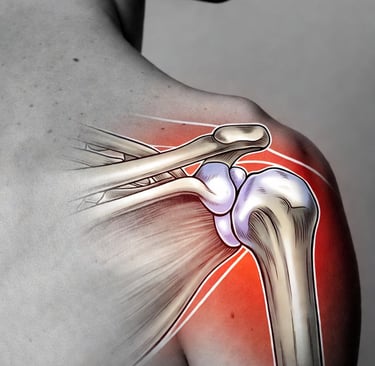

La capsulite rétractile est une inflammation de la capsule articulaire de l’épaule, cette enveloppe fibreuse qui entoure l’articulation. Elle provoque une rigidité progressive, comme si votre épaule « gelait » littéralement. Contrairement à une simple tendinite, cette pathologie évolue en phases distinctes :

L’embolisation de la capsulite rétractile est une innovation récente qui cible la cause profonde de l’inflammation : l’hypervascularisation. Dans une épaule gelée, de petites artères anormales se développent autour de la capsule, alimentant le processus inflammatoire et la douleur.